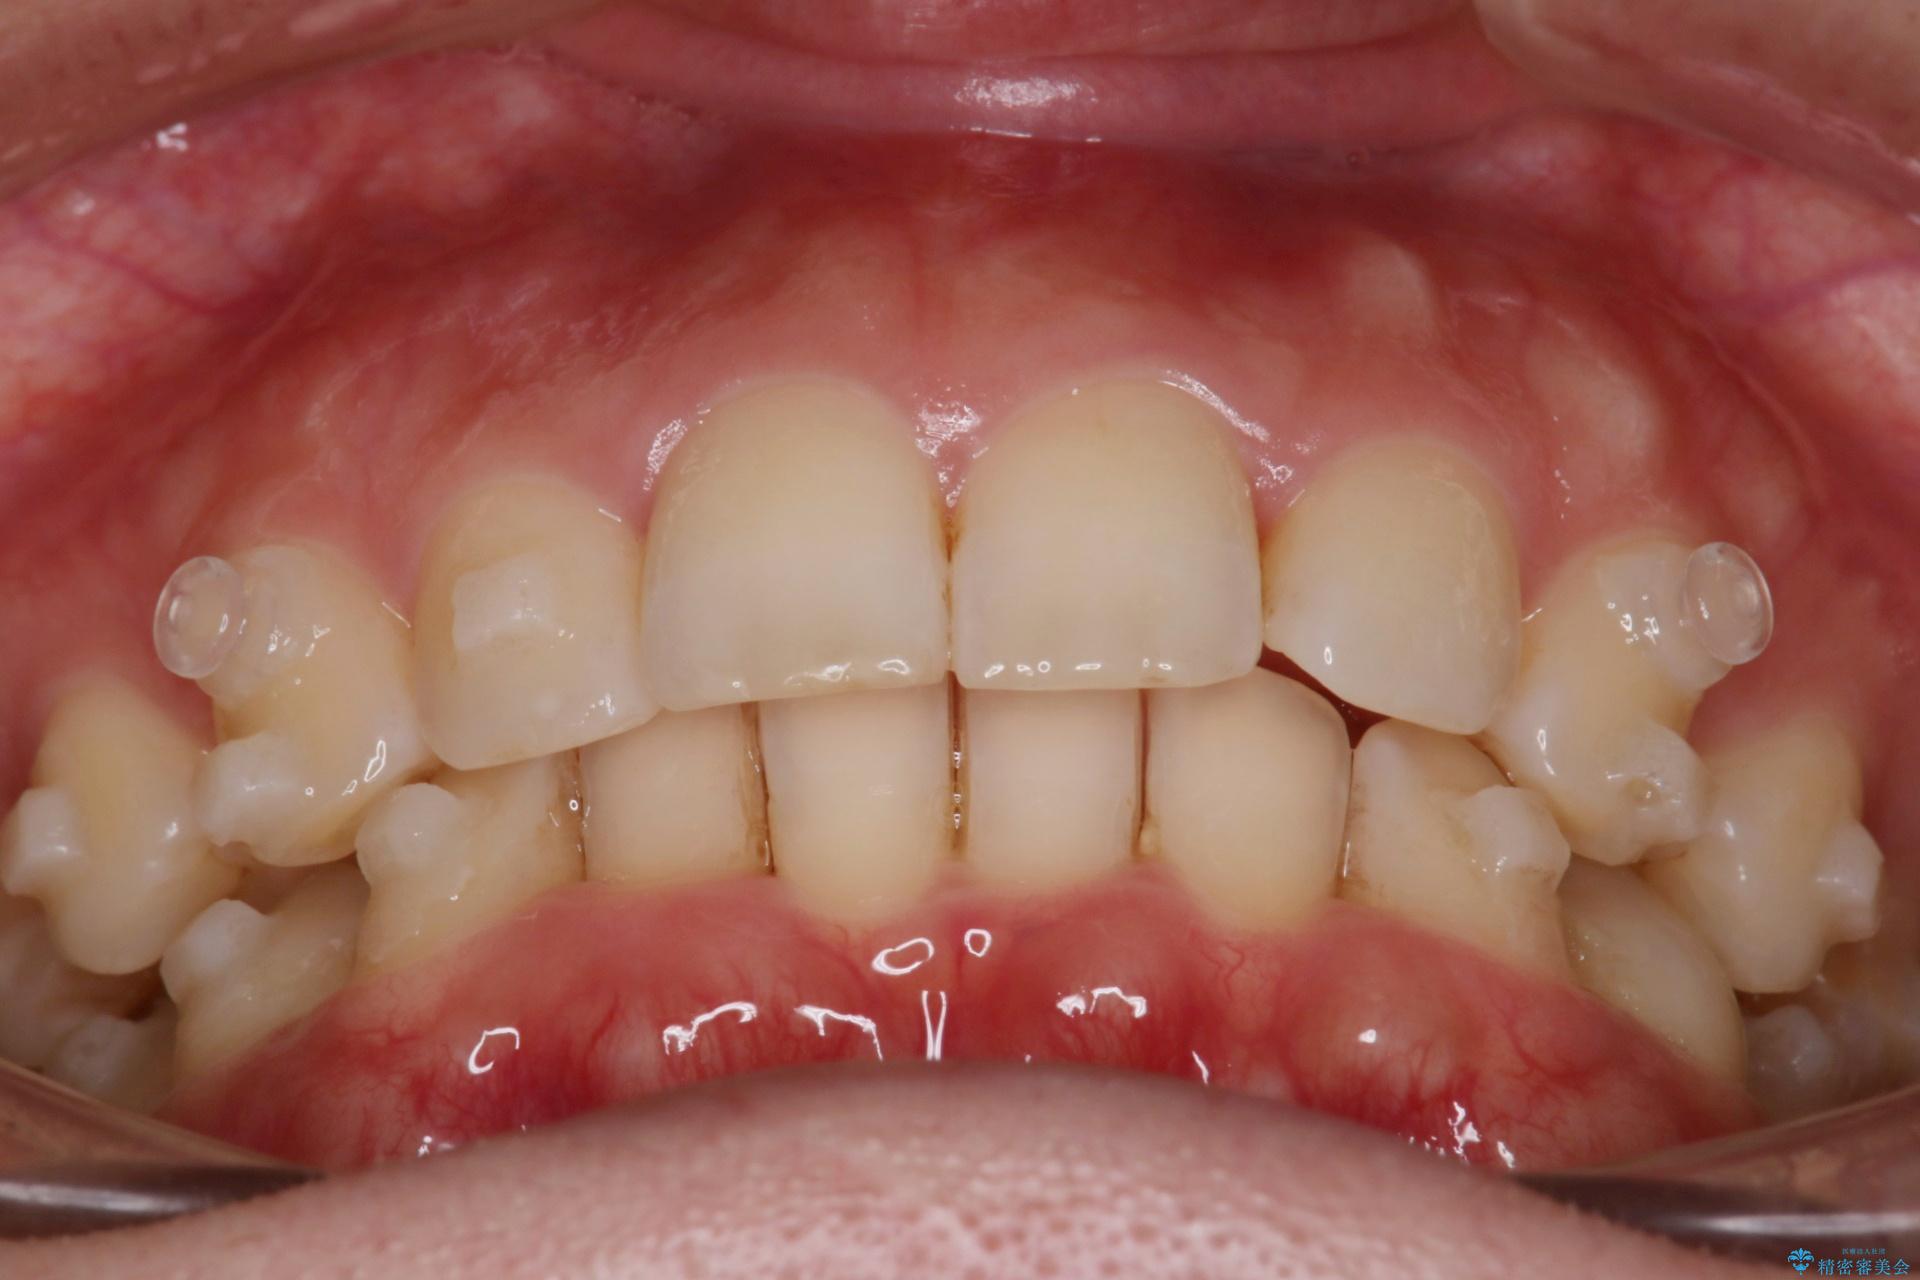

- 下の歯のがたつきを主訴に来院されました。

下の歯のがたつきと右の奥歯の噛みあわせ改善するために治療計画を立てることにしました。

噛み合わせをよくするために、ワイヤー矯正とインビザライン矯正のどちらの期間も必要な箇所にゴム掛けを行いながら治療を行いました。

下の前歯のがたつき改善にはIPR(歯と歯の間を削る処置)を行いました。

ゴム掛けを頑張っていただいたので、噛みあわせも改善され綺麗な歯並びになりました。